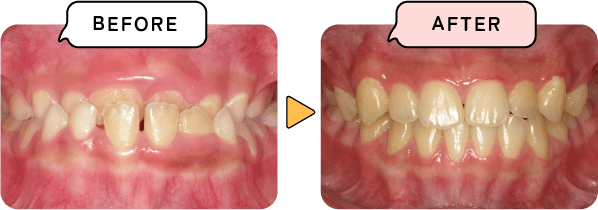

悪い歯並び・噛み合わせを何もしないで放置してしまうと不適切な状態で発育が進み、口の中だけでなく全身の発育や健康に悪影響を及ぼします。歯並びは子供一人一人に個性があります。矯正を必要とする歯並びもあれば、必要としない歯並びもあります。まずはお口の中を見せてください。そして不安なことを一緒に解決してきましょう。

歯が大きくなり、あごが小さくなることでスペースが足りず前後にデコボコした歯並びになります。

矯正の方法はたくさんありますが、当院では歯並びとからだ全体を健康にする「子ども顎顔面矯正」を中心にお子様の状態に合わせて、治療方法をご提案いたします。

お子様の成長発育に合わせて、本来あるべき正しい噛み合わせの状態を作ります。歯並びだけでなく、骨格矯正も含めた治療です。

骨格矯正をすることで、あごや顔・鼻腔の正常な発育をサポートします 。「歯並び」だけでなく「からだ全体」を健康にする矯正方法です。